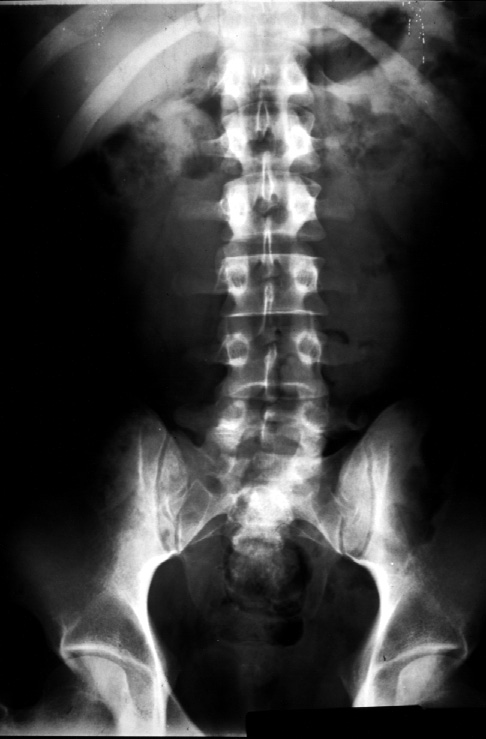

Radiology of Abdomen, Pelvis, and Perineum -- Normal Abdominal Film (KUB)

Identify -- antrum of the stomach, transverse colon, sigmoid colon, psoas

muscle, left kidney